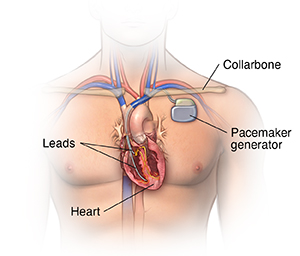

A pacemaker is a small device implanted in the chest. It sends electrical signals to start or regulate a slow heartbeat. It's most often placed in the chest just under the collarbone. A pacemaker may be used if the heart's natural pacemaker (the SA node) is not working correctly, causing a slow heart rate or rhythm, or if the electrical pathways are blocked.

A typical pacemaker or ICD has three main parts:

A pulse generator with a sealed lithium battery. It sends out the electrical signals that make the heart beat, or it sends out an electrical shock. Most generators can also receive and respond to signals sent by the heart itself.

One or more wires (leads). Leads are insulated flexible wires. They conduct electrical signals between the heart and the pulse generator. One end of the lead is attached to the pulse generator, and the electrode end of the lead is positioned in the heart. In the case of a biventricular pacemaker, leads are placed on both ventricles.

Electrodes. These are found on each lead.

Pacemakers that pace either the right atrium or the right ventricle are called "single-chamber" pacemakers.

Pacemakers that pace both the right atrium and right ventricle of the heart and need two pacing leads are called "dual-chamber" pacemakers.

Pacemakers that pace the right and left ventricles are called "biventricular" pacemakers.

Your doctor will make a small incision just under the collarbone. They will insert the pacemaker or ICD lead or leads into the heart through a blood vessel that runs under the collarbone. Once the lead is in place, your doctor can test it to make sure it is in the right place and is working. They then attach the lead to the generator (battery), which is placed just under the skin through the incision made earlier. Your doctor will close the incision with stitches, staples, or a medical glue (adhesive) and apply a dressing. Once the procedure has been completed, you will go through a recovery period of several hours.